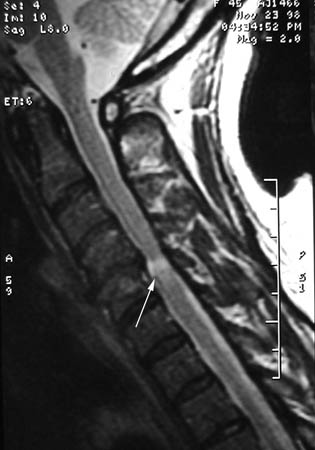

Doença degenerativa da coluna cervical

Um único nível de compressão da medula espinhal com alterações em T2, na sequência sagital cervical de T2 na presença de mielopatia cervical degenerativa sintomática

Dennis A. Turner, MA, MD